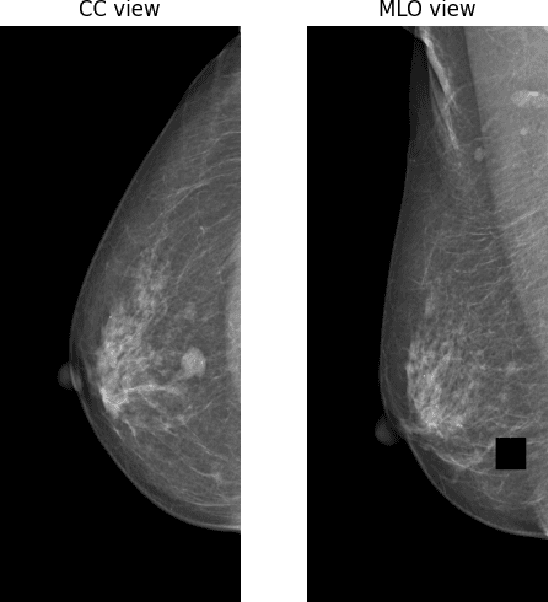

Screening mammography is the most widely used method for early breast cancer detection, significantly reducing mortality rates. The integration of information from multi-view mammograms enhances radiologists' confidence and diminishes false-positive rates since they can examine on dual-view of the same breast to cross-reference the existence and location of the lesion. Inspired by this, we present TransReg, a Computer-Aided Detection (CAD) system designed to exploit the relationship between craniocaudal (CC), and mediolateral oblique (MLO) views. The system includes cross-transformer to model the relationship between the region of interest (RoIs) extracted by siamese Faster RCNN network for mass detection problems. Our work is the first time cross-transformer has been integrated into an object detection framework to model the relation between ipsilateral views. Our experimental evaluation on DDSM and VinDr-Mammo datasets shows that our TransReg, equipped with SwinT as a feature extractor achieves state-of-the-art performance. Specifically, at the false positive rate per image at 0.5, TransReg using SwinT gets a recall at 83.3% for DDSM dataset and 79.7% for VinDr-Mammo dataset. Furthermore, we conduct a comprehensive analysis to demonstrate that cross-transformer can function as an auto-registration module, aligning the masses in dual-view and utilizing this information to inform final predictions. It is a replication diagnostic workflow of expert radiologists